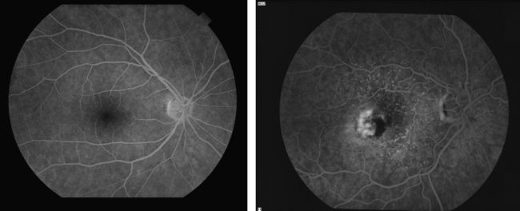

Fluorescein angiography, a test using an intravenous dye and photography to analyze retinal blood vessels, is often used to diagnose wet AMD. The results of this test help determine treatment options for patients with wet AMD.

LEFT: Fluorescein angiography showing a normal macula RIGHT: Fluorescein angiography showing wet AMD

LEFT: Fluorescein angiography showing a normal macula

RIGHT: Fluorescein angiography showing wet AMD